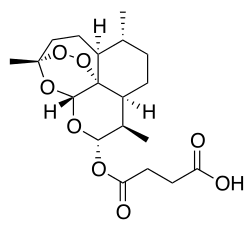

| Formula | C19H28O8 |

| Molar mass | 384.425 g·mol−1 |

| 3D model (JSmol) | |

Chemical synthesis

Artesunate is made from dihydroartemisinin (DHA) by reacting it with succinic acid anhydride in a basic medium. It is one of few semi-synthetic derivatives from artemisinin that is water-soluble.[37][39]